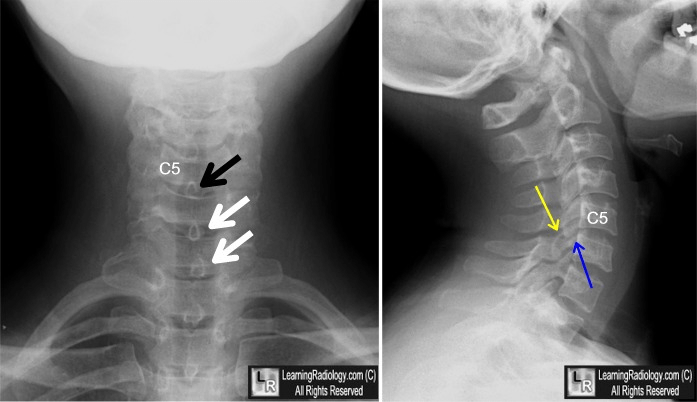

The pathology seen on these images.

What are facet locks? (SP not in straight line), anterior displacement of spine)